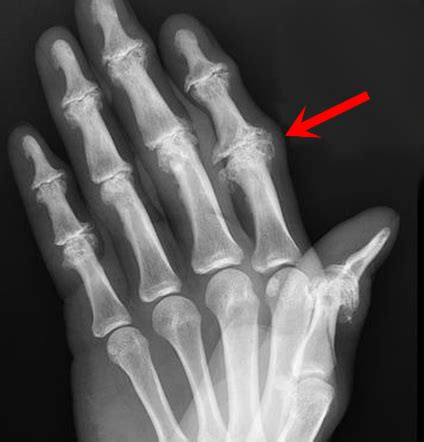

Heberdens Nodes Xray

Discover the most common types of arthritis in hands, including osteoarthritis, rheumatoid arthritis, and psoriatic arthritis. Learn to recognize early symptoms like joint pain, stiffness, and swelling. Our comprehensive guide helps you understand these conditions, explore effective treatment options, and find relief to improve your hand mobility and quality of life.